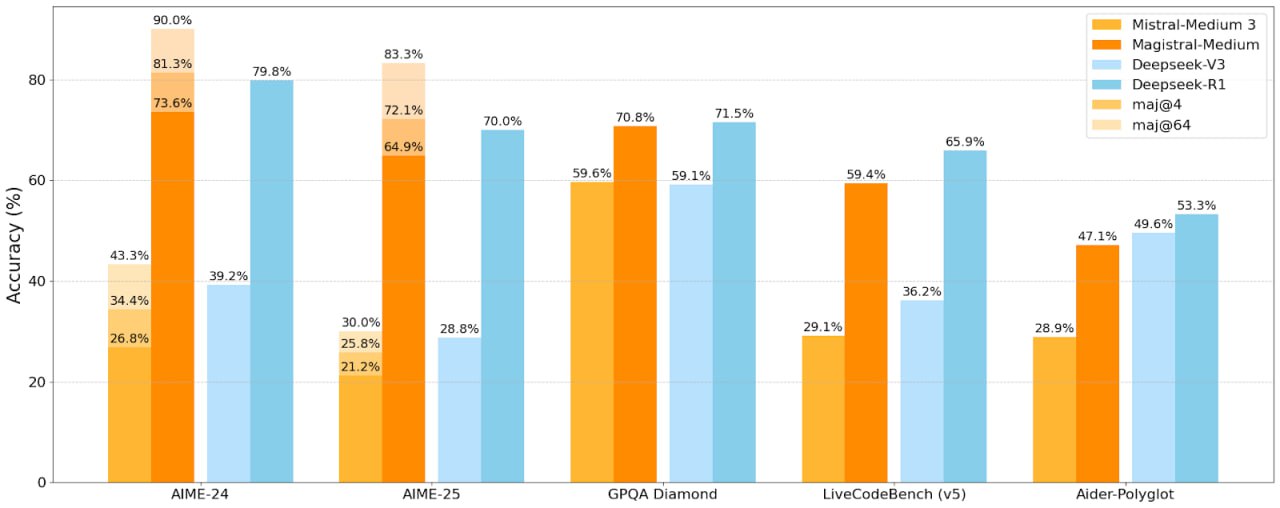

Важные ячейки сигнализирует об опасности Небольшая миндалевидная область мозга, называемая миндалевидным телом, связывает эмоции с воспоминаниями, обучением и нашими чувствами. Поэтому неудивительно, что этот регион играет важную роль в принятии решения о том, какие вкусы мы считаем отвратительными, а какие нет.

Группа Палмитера доказала, что кишечник сообщает мозгу, когда он чувствует себя отвратительно. Как? Это активирует определенные “тревожные” нейроны, называемые CGRP-клетками. “Они реагируют на все плохое”, — объясняет Пальмитер.

Когда мышам впервые стало плохо после употребления виноградного Kool-Aid, у них включились сигнальные нейроны. Это событие повысило чувствительность клеток миндалевидного тела, которые хранили воспоминания о вкусе винограда.

Те же клетки миндалевидного тела также активизировались, когда мыши снова попробовали виноградный Kool-Aid. Это говорит о том, что сигнальные нейроны помогли миндалевидному телу запомнить продукты, которые казались опасными.